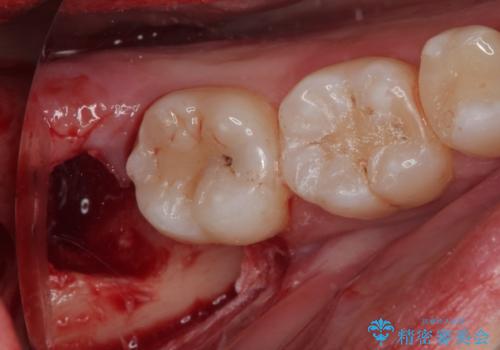

- 当院でセラミック治療を行い、その後に親知らずを抜きたいとのことで来院された患者様です。

CTで神経の位置などを確認し、抜歯術を行いました。

一週間後に抜糸を行いました。